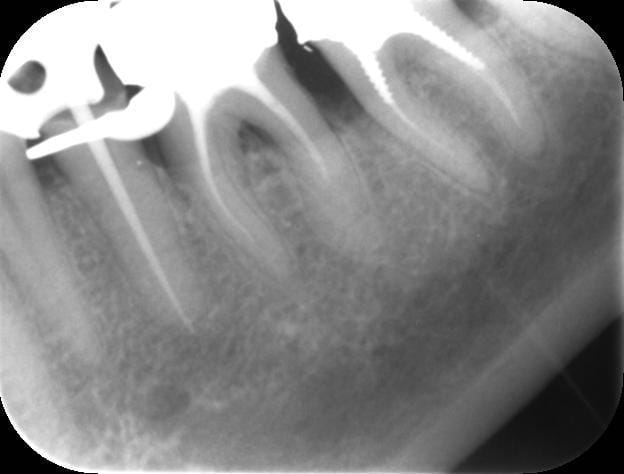

RTE avec le réciproc, c'est vraiment trop simple.

4697 20131031 15 04 49 fx3fdq - Eugenol

4697 20131031 15 36 51 ogmuid - Eugenol

4697 20131031 15 29 47 cnltm7 - Eugenol